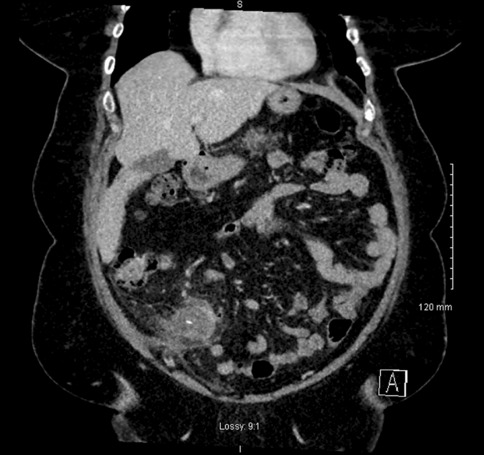

Methods: 3D virtual models were created through manual segmentation of CT and MRI scans obtained according to protocols routinely used in colorectal cancer staging. No extra patient time or preparation were needed. CT and MRI images were analysed by Gastrointestinal Radiologist to delineate the tumour and provide the cancer staging. Manual segmentation was then performed in 3D Slicer, an open-source, free software used for creation of three-dimensional anatomical models. Additional post-processing was applied in MeshLab or Blender.

Results: Ten 3D models depicting tumour deposits in colorectal cancer were created. Models of right- and left-sided bowel cancer with tumour deposits were derived from CT scans, while those of rectal cancer—from MRI scans. 3D models depicted bowel with the tumour and tumour deposits, relevant vasculature and lymph nodes, as well as surrounding structures as required. Models can be manipulated to allow for most comprehensible inspection of different anatomical structures and relationships. The transparency of each structure can be changed. The morphological appearance of tumour deposits and their relation to vessels can be readily appreciated. The morphological differences between the tumour deposits and lymph nodes, both benign and metastatic, can also be evaluated.

Conclusions: This work follows on from our previous experience with exploration of 3D modelling technology to map tumour deposits in rectal cancer, based on rectal MRI images. This innovative technology shows a huge potential to enhance our understanding of surgical pathology. It can provide a welcome assistance in exploring new concepts and developing new theories. It can facilitate communication and discussion around the evolving concepts. It is a versatile novel tool which can be successfully applied for depiction of tumour deposits in any part of the bowel. Here we showed its feasibility for the use in left- and right-sided bowel cancer, in addition to previously explored rectal cancer. It can utilise modalities commonly used in colorectal cancer staging – CT and MRI, which renders it clinically applicable. While there is an ongoing debate on the correct classification of tumour deposits and their full significance in metastatic process, as well as their prognostic value, 3D technology can facilitate familarisation with their appearance. It can also become an educational tool both for radiologists and surgeons and a valuable adjunct in the multidisciplinary management of colorectal cancer.